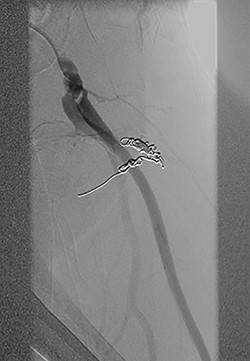

Vascular surgery was consulted and CT angiography demonstrated a large DFA pseudoaneurysm (Fig. 4A and B). Given her advanced years and comorbidities, a minimally invasive approach was recommended. The pseudoaneurysm was successfully embolized using numerous microcoils (Fig. 5). Completion angiography demonstrated complete occlusion of the pseudoaneurysm and patent superficial and DFA (Fig. 5). There were no immediate complications. After discussion with the patient, it was agreed that restarting her apixaban increased risk for her hematoma rebleeding and no anticoagulation was continued for stroke prevention.

(A and B): Frontal digitally subtracted angiography via a diagnostic catheter positioned in the proximal left DFA demonstrating a large pseudoaneurysm originating from a small DFA branch. The long, narrow and lobulated pseudoaneurysm neck can be see coursing along the cranial aspect of the pseudoaneurysm.